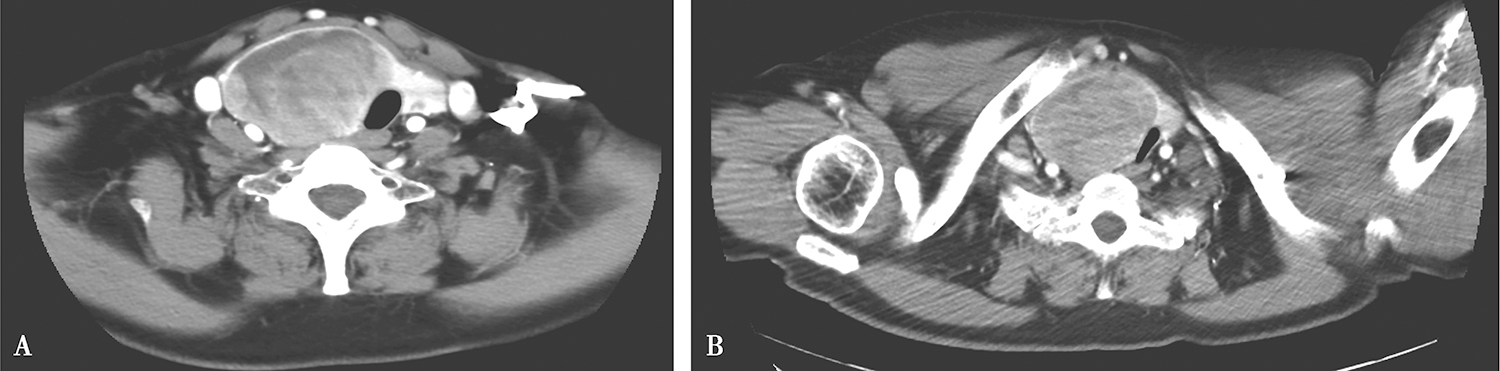

2.2017年3月10日颈胸部CT

甲状腺增大,其内多发结节及肿物,以右侧病变明显,约5.2cm×6.7cm,边界清楚,部分伸入纵隔,增强后实质性成分中等略不均匀强化,部分区域可见坏死(图2)。双侧颈深链及颈后三角区可见多发淋巴结肿大,大者短径约0.8cm,锁骨上、纵隔未见明确肿大淋巴结。右下肺条索,余肺内未见明确异常,心包、胸腔未见积液。

图2 颈部增强CT示甲状腺右叶肿物部分伸入上纵隔

影像学诊断:

(1)甲状腺右叶肿物,伸入纵隔,腺瘤?结节性甲状腺肿伴腺瘤样增生?

(2)颈部多发淋巴结肿大,良性可能大。

(3)右下肺慢性炎性条索。